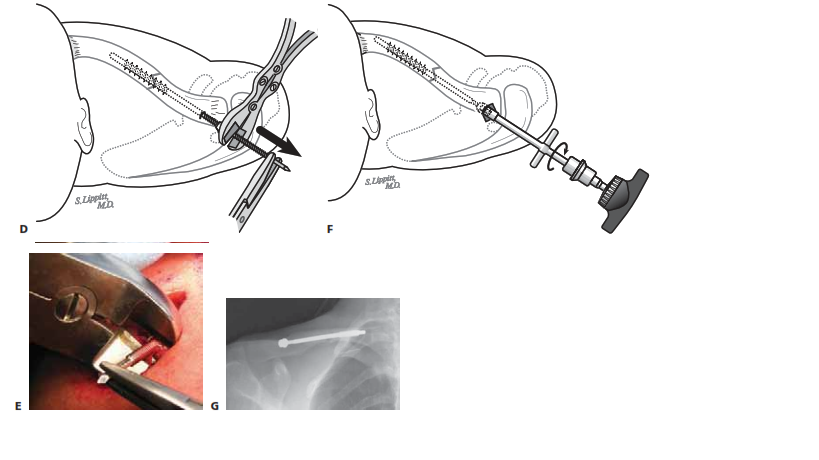

Preparation of the medullary canal is the most technically demanding phase of the operation. The technique described herein utilizes a robust intramedullary device, such as the modified Hagie pin or the Rockwood Clavicle Pin. A bone-reducing clamp or a pointed Weber towel clip is applied to the medial fragment to elevate it into the surgical wound. Due to the dense trabecular nature of the clavicular medulla, the canal must be sequentially sized and drilled. Using the appropriate-size drill bit or hand reamer, the canal of the medial fragment is prepared. The C-arm is utilized extensively during this step to confirm the trajectory of the drill, ensuring it remains perfectly centered within the canal and does not breach the anterior or posterior cortices. The medial canal is typically prepared to a depth of approximately 3 to 4 centimeters.

Attention is then turned to the lateral fragment. The lateral fragment is elevated, and the drill is introduced into its medullary canal. The drill is advanced laterally and slightly posteriorly, following the natural curve of the bone, until it intentionally breaches the posterolateral cortex of the clavicle, exiting posteriorly to the acromioclavicular joint. This exit point must be carefully monitored with fluoroscopy to ensure it does not compromise the AC joint capsule or penetrate the suprascapular nerve.

Once both fragments are adequately prepared, the intramedullary pin is introduced. The blunt end of the pin is passed retrograde into the drilled canal of the lateral fragment. It is advanced laterally using a T-handle or power drill until the medial end of the pin is flush with the fracture site. The surgeon then meticulously reduces the fracture. This often requires a combination of direct manipulation of the fragments with bone clamps, lateral traction on the arm, and posterior translation of the shoulder girdle. Once anatomical cortical apposition is achieved and verified fluoroscopically, the pin is driven antegrade across the fracture site and into the prepared medial fragment.

The pin is advanced until the lateral threaded portion engages the dense bone of the posterolateral cortex. To definitively prevent medial migration—a historical complication of smooth pins—a low-profile locking nut is threaded onto the lateral end of the pin and seated firmly against the posterolateral cortex. The excess pin is then cut flush with the nut to minimize soft tissue irritation. Final orthogonal fluoroscopic images are obtained to confirm excellent fracture reduction, appropriate implant length, and the absence of cortical breaches. The wound is irrigated copiously, the platysma is repaired with absorbable suture to prevent a widened scar, and the skin is closed with a subcuticular stitch.

Clinical & Radiographic Imaging Archive